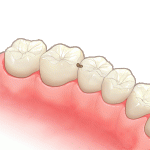

①虫歯があります

-

②虫歯を削り型取りします